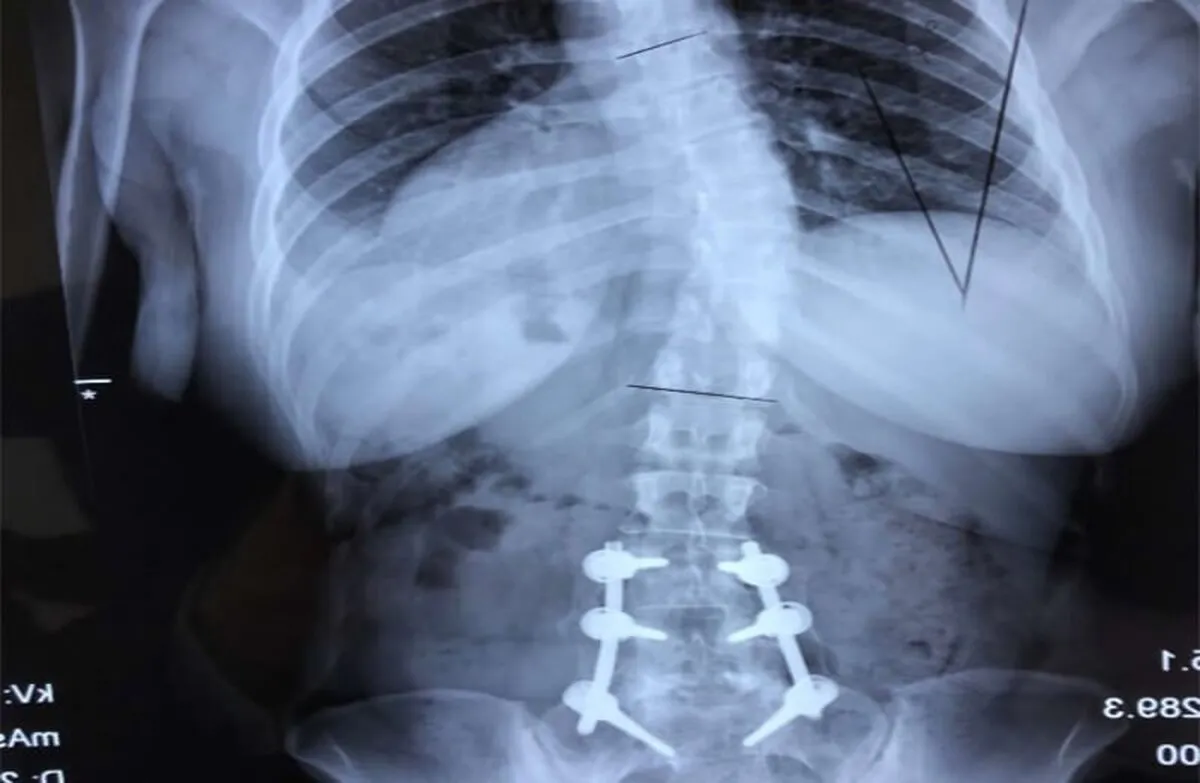

2.برنامهریزی جراحی: در مواردی که جراحی لازم باشد، جراح ستون فقرات باید نوع و ماهیت جراحی را برنامهریزی و اجرا کند. این جراحیها ممکن است شامل جراحی تعویض مهره، انفصال جدایی مهرهها (اسکولیوزیس)، یا جراحیهای ترمیمی دیگر باشند.

3.جراحی ستون فقرات: جراح ستون فقرات با استفاده از تکنیکهای جراحی پیشرفته و تجهیزات مناسب جراحیهای پیچیده را انجام میدهد. این جراحیها معمولاً با هدف تخریب بافتهای تخریب شده، استحکامبخشی به ستون فقرات، و بهبود عملکرد بیمار انجام میشوند.